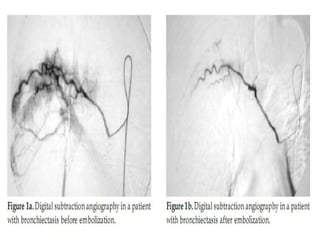

Bronchial artery embolization